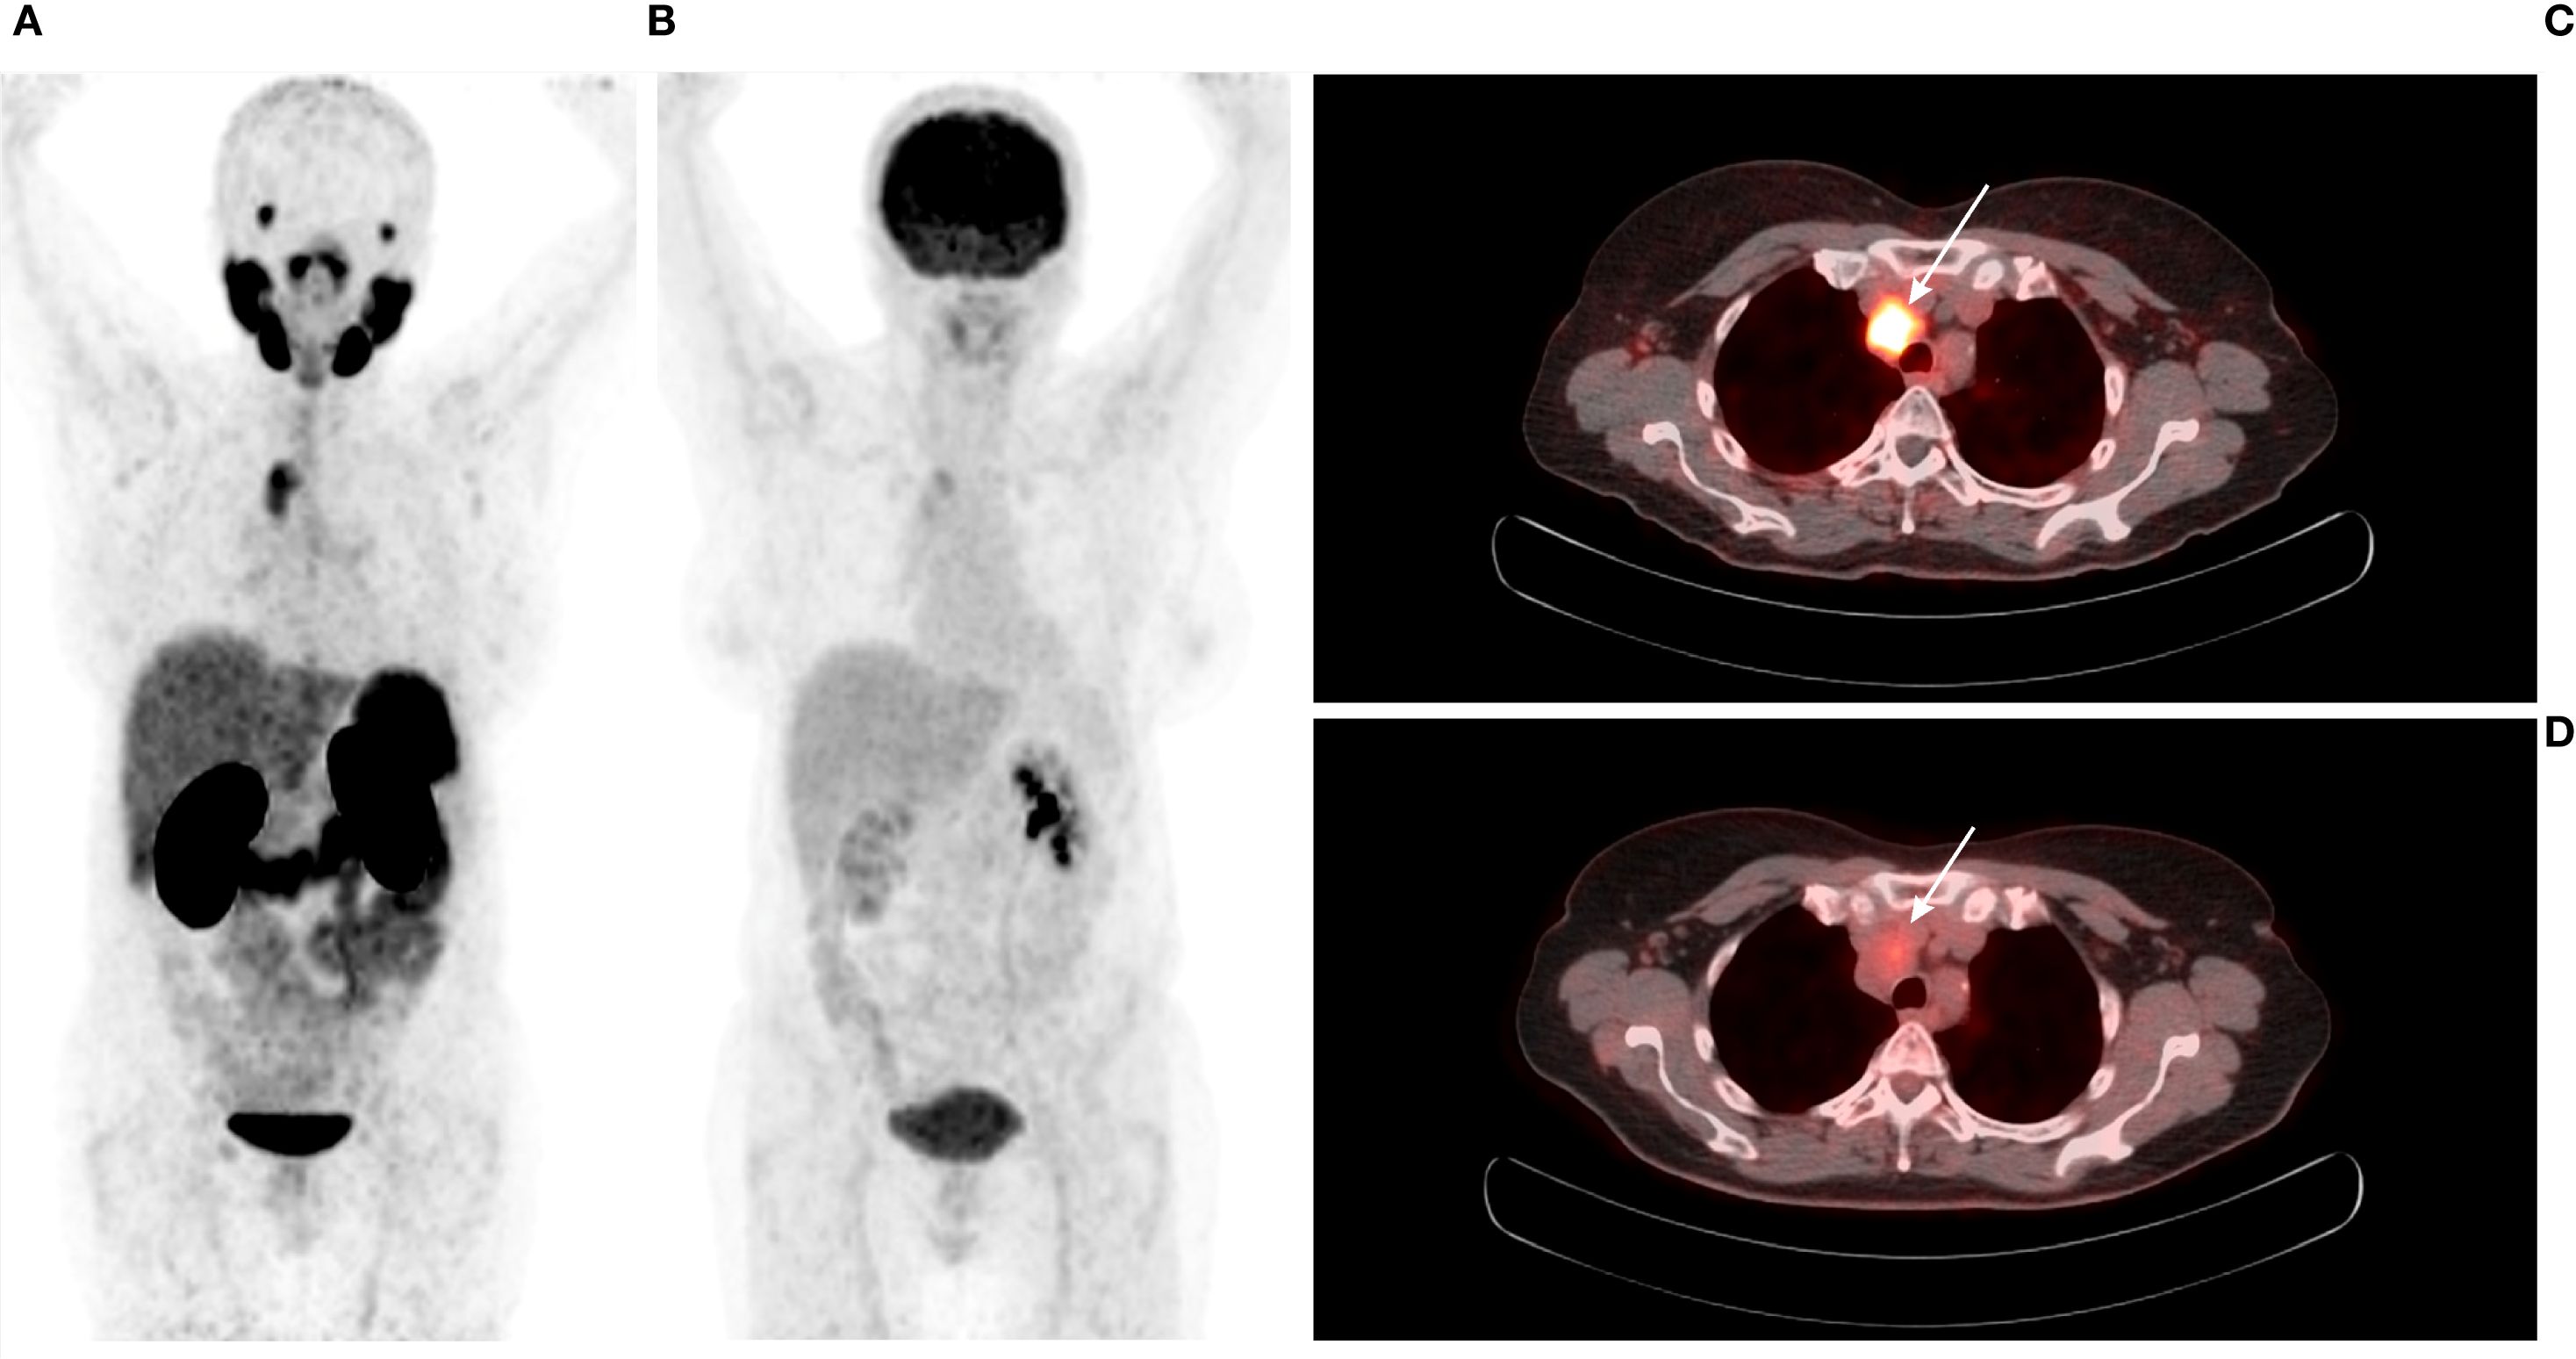

[68Ga]Ga-PSMA-11 PET/CT was positive in 5/12 patients – 3/3 patients with previously-identified structural lesions (a superior mediastinal mass, a metastatic cervical lymph node, and liver metastases; Figures 3–5) and 2/9 patients without previously known structural lesions. In both of these cases, [68Ga]Ga-PSMA-11 PET/CT revealed small lesions in the thyroidectomy bed, which could correspond to local recurrence or lymph nodes (one shown in Figure 6). The mean SUVmax, TBRBlood and TBRLiver values for detected lesions were 7.08 (range 2.74–12.37), 6.08 (range 3.19–9.82), and 2.23 (range 0.90–3.77), respectively.

Figure 4. (A) 74-year-old male with medullary thyroid carcinoma and cervical metastatic lymph nodes. Transaxial (A, B) and sagittal (C, D) views of the fused [68Ga]Ga-PSMA-11 PET/CT and PET scans (white arrows). The metastatic lymph node in the left IIb neck compartment demonstrates abnormal [68Ga]Ga-PSMA-11 uptake (SUVmax 3.49; TBRBlood 3.79). The patient underwent left cervical lymph node dissection. Histopathological examination confirmed metastasis of medullary thyroid carcinoma.